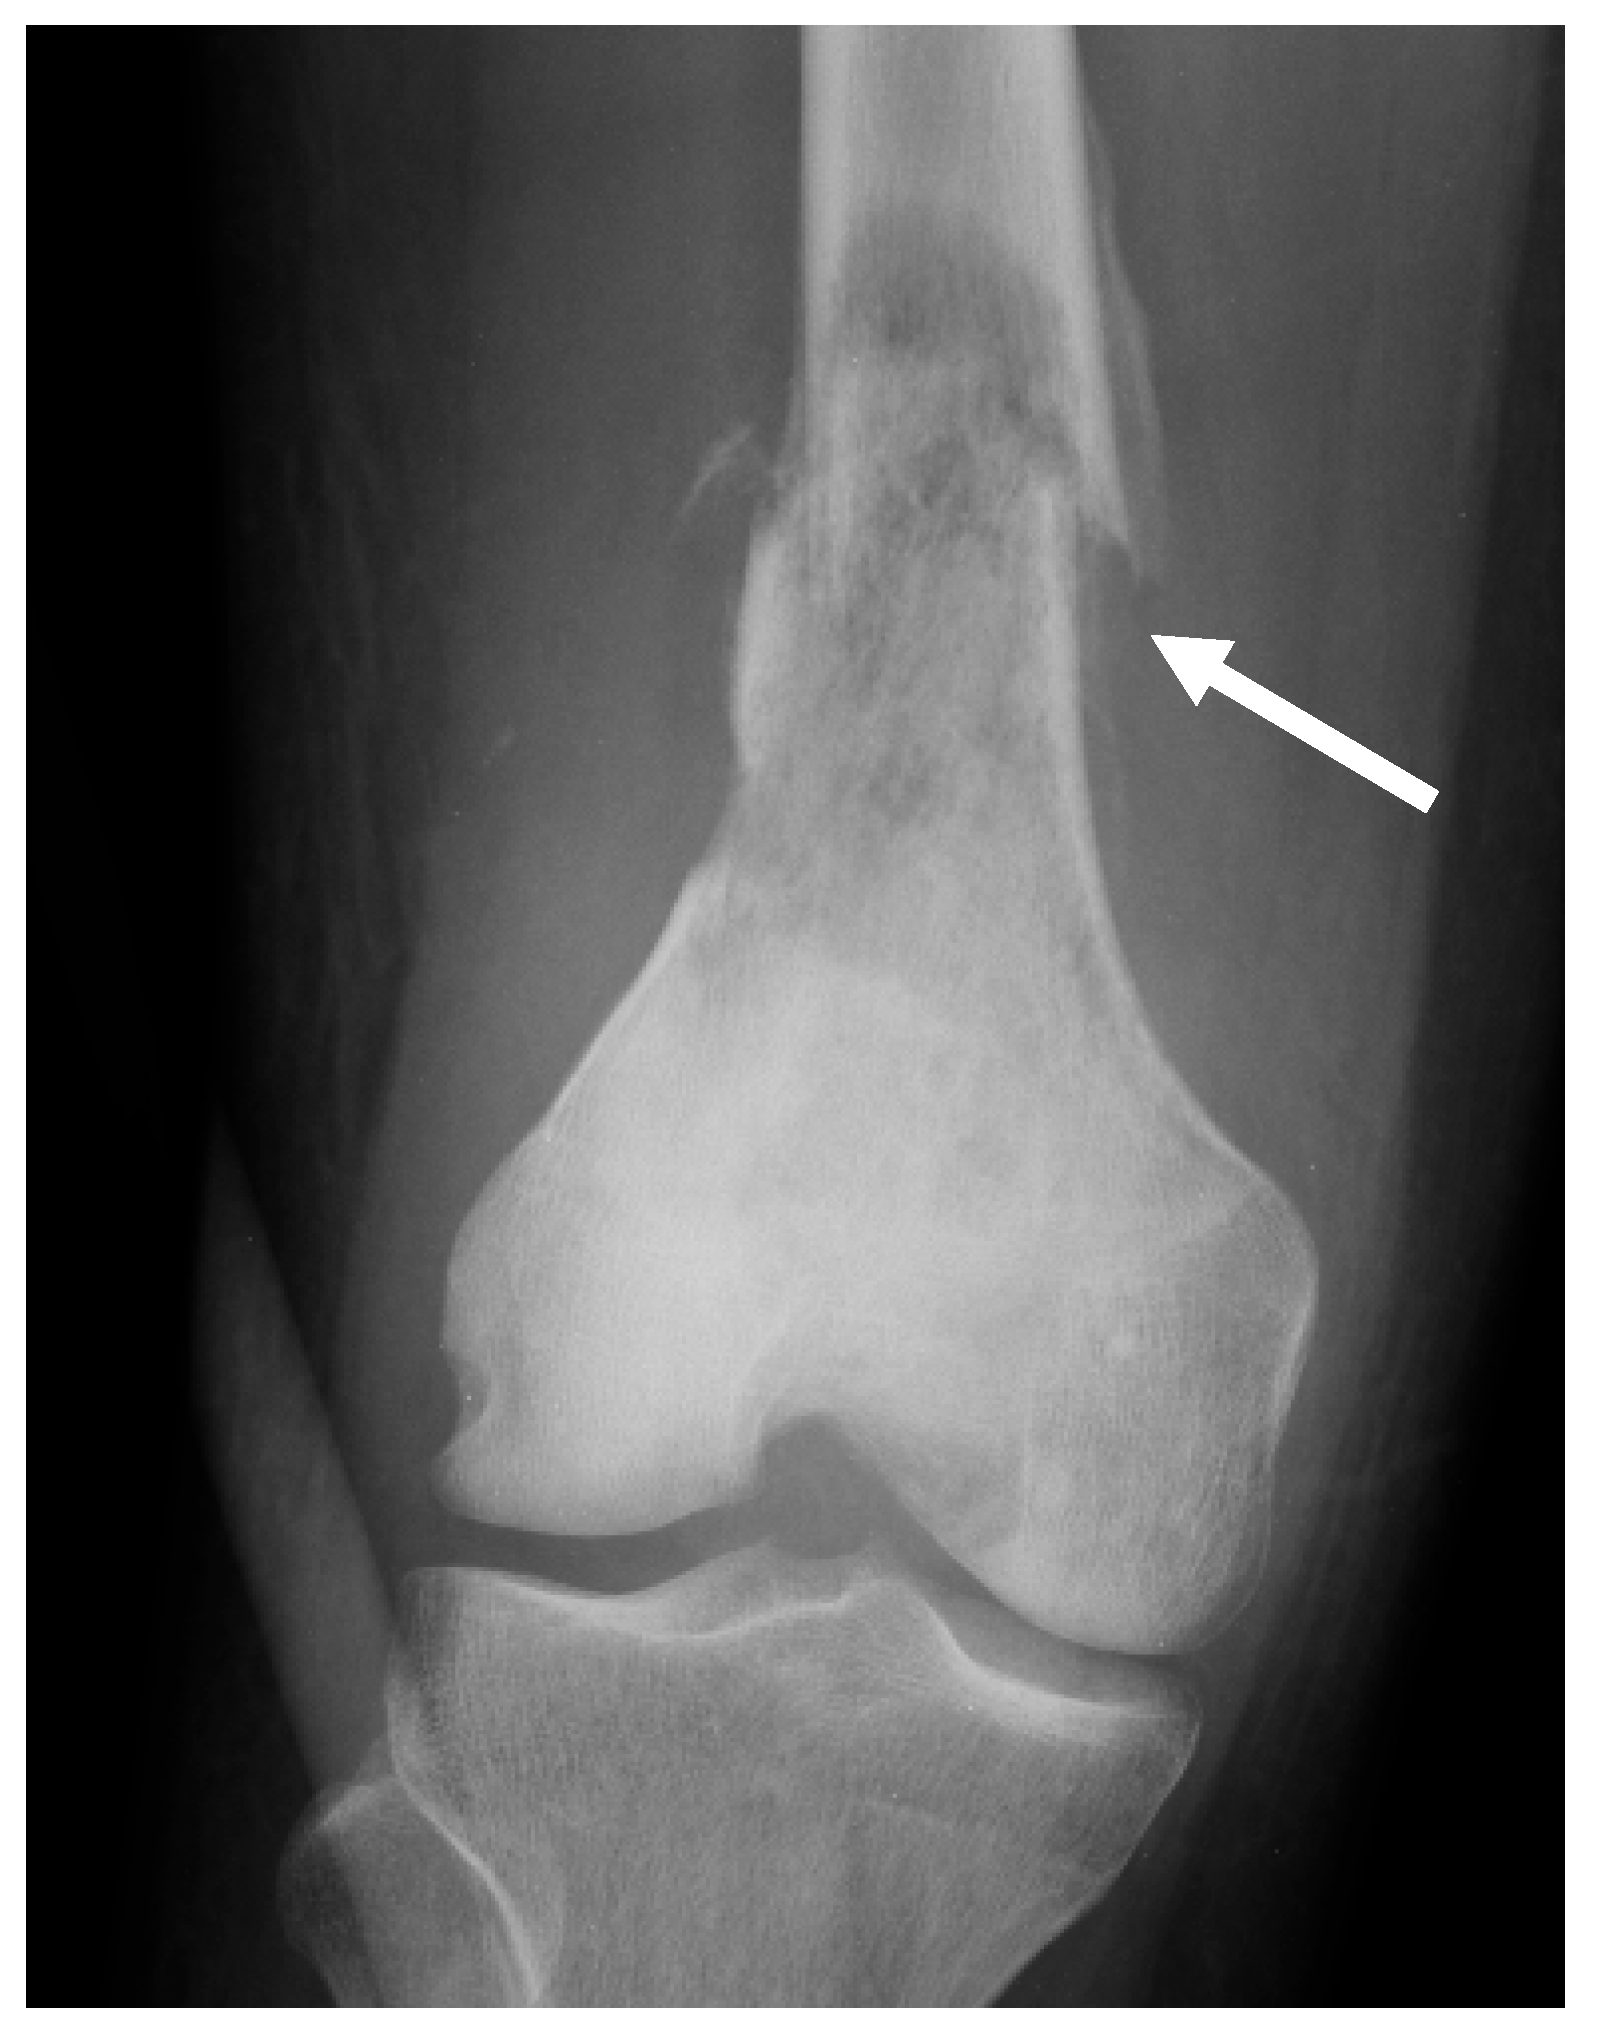

| Conventional osteosarcoma | Mixed (lytic and sclerotic) or completely eburneous | Sunburst, Codman triangle, other irregular/aggressive types | Soft-tissue components frequently displayed |

| Conventional high-grade osteosarcoma 1 | 75–80% | 10–20 years old; M:F = 1.5:1 | Distal femoral bone, proximal tibia, or humerus (70%) |